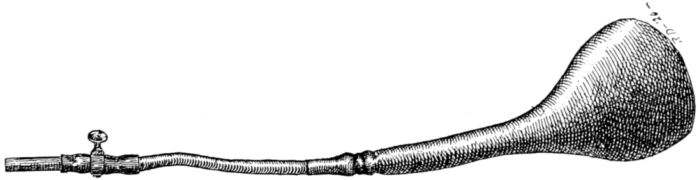

| 111. | Rubber bougie | 311 |

| 112. | Champetier de Ribes’ bag | 311 |